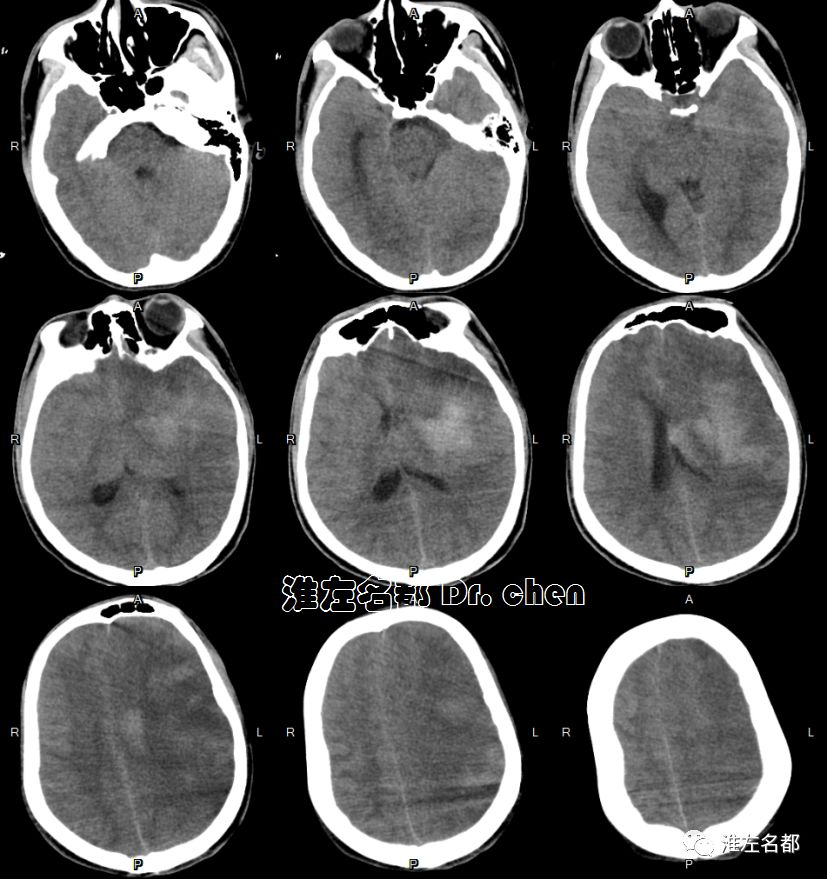

急诊多模式CT

△头颅CT平扫:左侧半球大范围低密度,灰白质分界消失,脑沟受压变小-消失;左侧大脑中动脉区ASPECT-2。

复查CT

2019-9-1 11:34

△颅脑CT平扫+增强:左侧基底节区和部分额叶呈稍高密度,左侧前循环血流通畅;左侧半球肿胀明显,脑室、脑沟和脑池受压,中线结构向右侧显著移位。

复查多模式CT

2019-9-2 11:47

△头颅CT平扫:左侧去骨瓣减压术后,左侧半球仍有肿胀,中线结构移位较前稍改善。

CT

2019-9-9

△头颅CT:左侧去骨瓣减压术后,中线结构居中,侧脑室受压较前改善。

2019-10-22

△头颅CT平扫:左侧去骨瓣减压术后,左侧半球大面积梗死组织坏死软化,左侧侧脑室扩大。

2019-12-20

△头颅CT平扫:左侧去骨瓣减压术后,左侧半球大面积陈旧性梗死软化灶,左侧侧脑室扩大。

2020-1-3

△头颅CT平扫:左侧半球大面积陈旧性梗死软化灶,左侧颅骨修补术后。